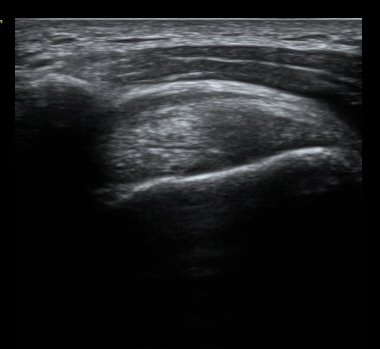

°ßºÀ ¿ÜÃø¿¡ ŽÃËÀÚ¸¦ ´ë°í ½ÃÇàÇÑ Ãæµ¹°Ë»ç¿¡¼­ °ßºÀ ¿ÜÃø¿¡ ¼ö¾×Àú·ù°¡ °üÂûµÇ¾ú´Ù.(±×¸² 9).

ÃÊÀ½ÆÄ°Ë»ç»ó °üÀý³» ¼ö¾×Àú·ù¸¦ º¸ÀÌÁö ¾Ê°í ÃÊÀ½ÆÄ °üÂûÇÏ ¿ÜÀü°Ë»ç¿¡¼­ °ßºÀ ¿ÜÃø¿¡

¼ö¾×Àú·ù°¡ °üÂûµÇ°í ȯÀÚÀÇ ¼öµ¿ÀûÀÎ ¿ÜÀü½Ã ÅëÁõÀ» º¸¿© Á¡¾×³¶³»¿¡ ÁÖ»çÄ¡·á¸¦ ½ÃÇàÇÏ¿´´Ù.